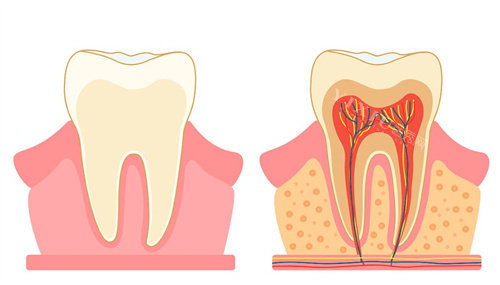

贝乐美口腔拥有一支正规的医疗团队,医生们均具备丰富的临床经验和扎实的正规知识。他们擅长各种口腔疾病的诊断和治疗,无论是常见的龋齿、牙周病,还是复杂的牙齿矫正、种植牙手术,都能为您提供优质的医疗服务。在治疗过程中,医生会详细为您讲解病情和治疗方案,让您充分了解治疗过程,放心接受治疗。此外,贝乐美口腔还引进了新型的口腔诊疗设备,如智能化全景X光机、口腔CT、激光治疗仪等,这些设备能够为医生提供更精细的诊断依据,提高治疗结果,缩短治疗时间,让您的看牙体验更加舒适。

贝乐美口腔提供齐全的口腔诊疗服务,涵盖了口腔内科、口腔外科、口腔正畸、口腔修复等多个领域。如果您有龋齿问题,可以在这里进行正规的补牙治疗;如果是牙齿缺失,可以选择种植牙或烤瓷牙修复;对于牙齿不齐的患者,贝乐美口腔提供多种牙齿矫正方案,包括传统的金属托槽矫正、陶瓷托槽矫正以及隐形矫正等,满足不同患者的需求。此外,诊所还提供牙齿美白、洁牙等美容项目,让您拥有更自信的笑容。